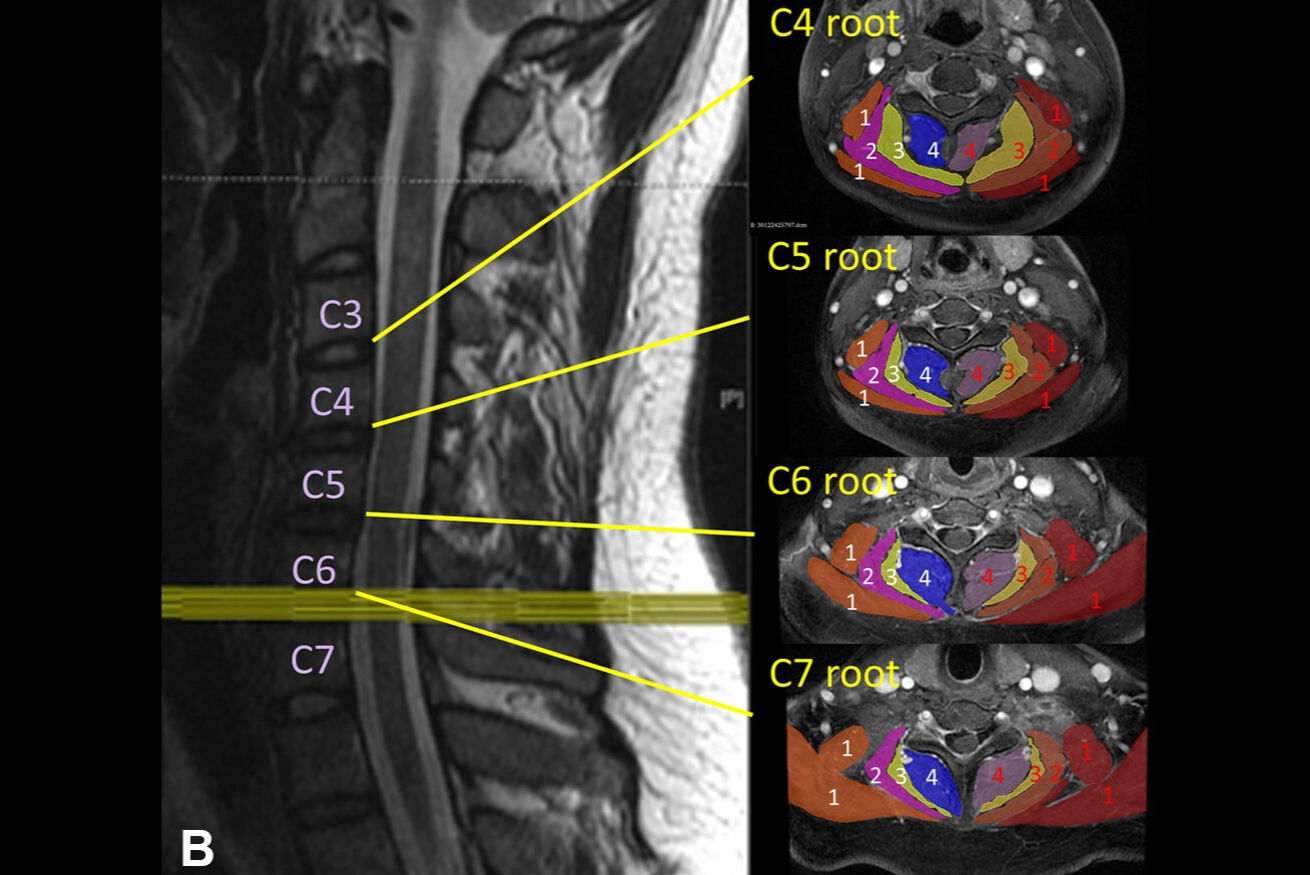

Ultrahigh-resolution ultrasound and MR neurography (which visualizes the peripheral nerves) can localize the problem and assess the severity of nerve damage and whether that damage has affected the muscles, according to the team.